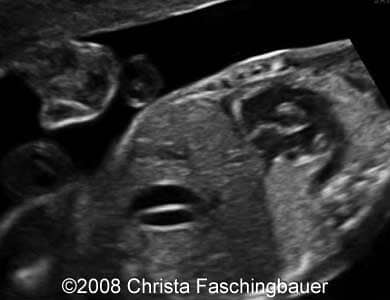

Gallbladder duplication Christa Faschingbauer, MD. Article Published: Jun 4, 2008 Germany Case report Following images and video show a case of the gallbladder duplication detected during the second trimester examination. Images 1, 2: Sagittal scans showing two gallbladders of the fetus. Video 1: Sagittal scan of the fetus with the gallbladder duplication. Sorry, your browser doesn't support embedded videos. Discussion Board Start a discussion about this article Add to Favorites Favorite